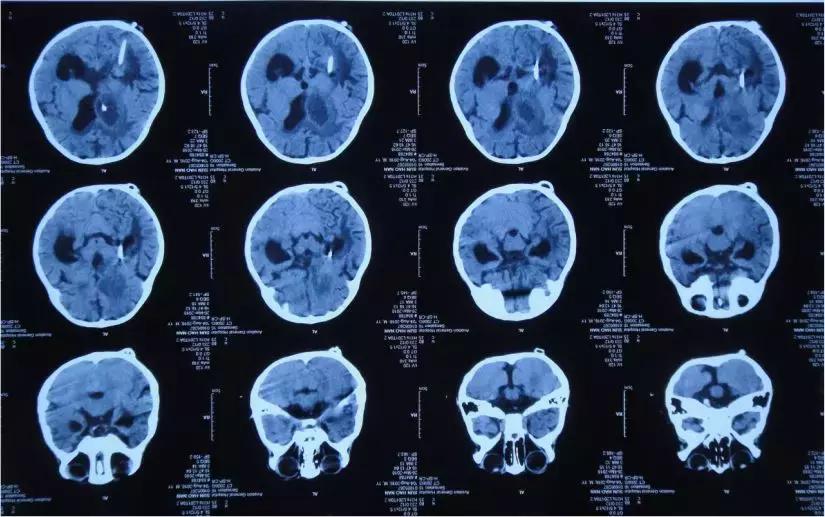

2018年3月26日头部影像检查

2018年3月26日入院当天

初步诊断: 1 中枢神经系统感染,2 脑膜炎,3 脑炎,4 脑室炎,5 脑室粘连,6 继发性脑积水,7 低钠血症,8 营养性贫血,9 脑脓肿。

李小勇主任指导意见:患儿诊断“1、脑积水 2、颅内感染 3、脑室粘连”明确。根据目前情况,需行开颅脑室探查术+透明隔造瘘术+侧脑室腹壁外引流术。疏通脑脊液循环通路,减轻脑组织压迫。